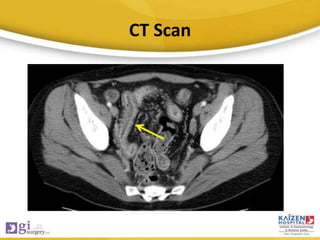

• CT Scan: Thickened terminal ileum/cecum.

CT Scan